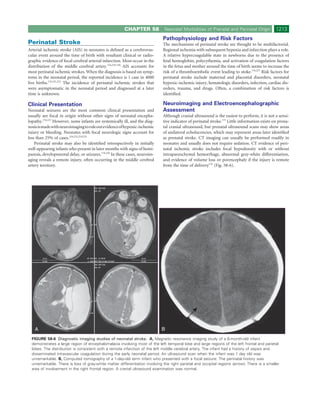

FIGURE 58-1 Estimated mortality risk by birth weight and gestational age based on singleton infants

born in National Institute of Child Health and Human Development (NICHD) Neonatal Research Network

centers between January 1, 1995, and December 31, 1996. Numeric values represent age- and weight-

specific mortality rates per 100 births. (From Lemons JA, Bauer CR, Oh W, et al: Very low birth weight

outcomes of the National Institute of Child Health and Human Development Neonatal Research Network,

January 1995 through December 1996. NICHD Neonatal Research Network. Pediatrics 107:E1, 2001. Used

with permission of the American Academy of Pediatrics.)